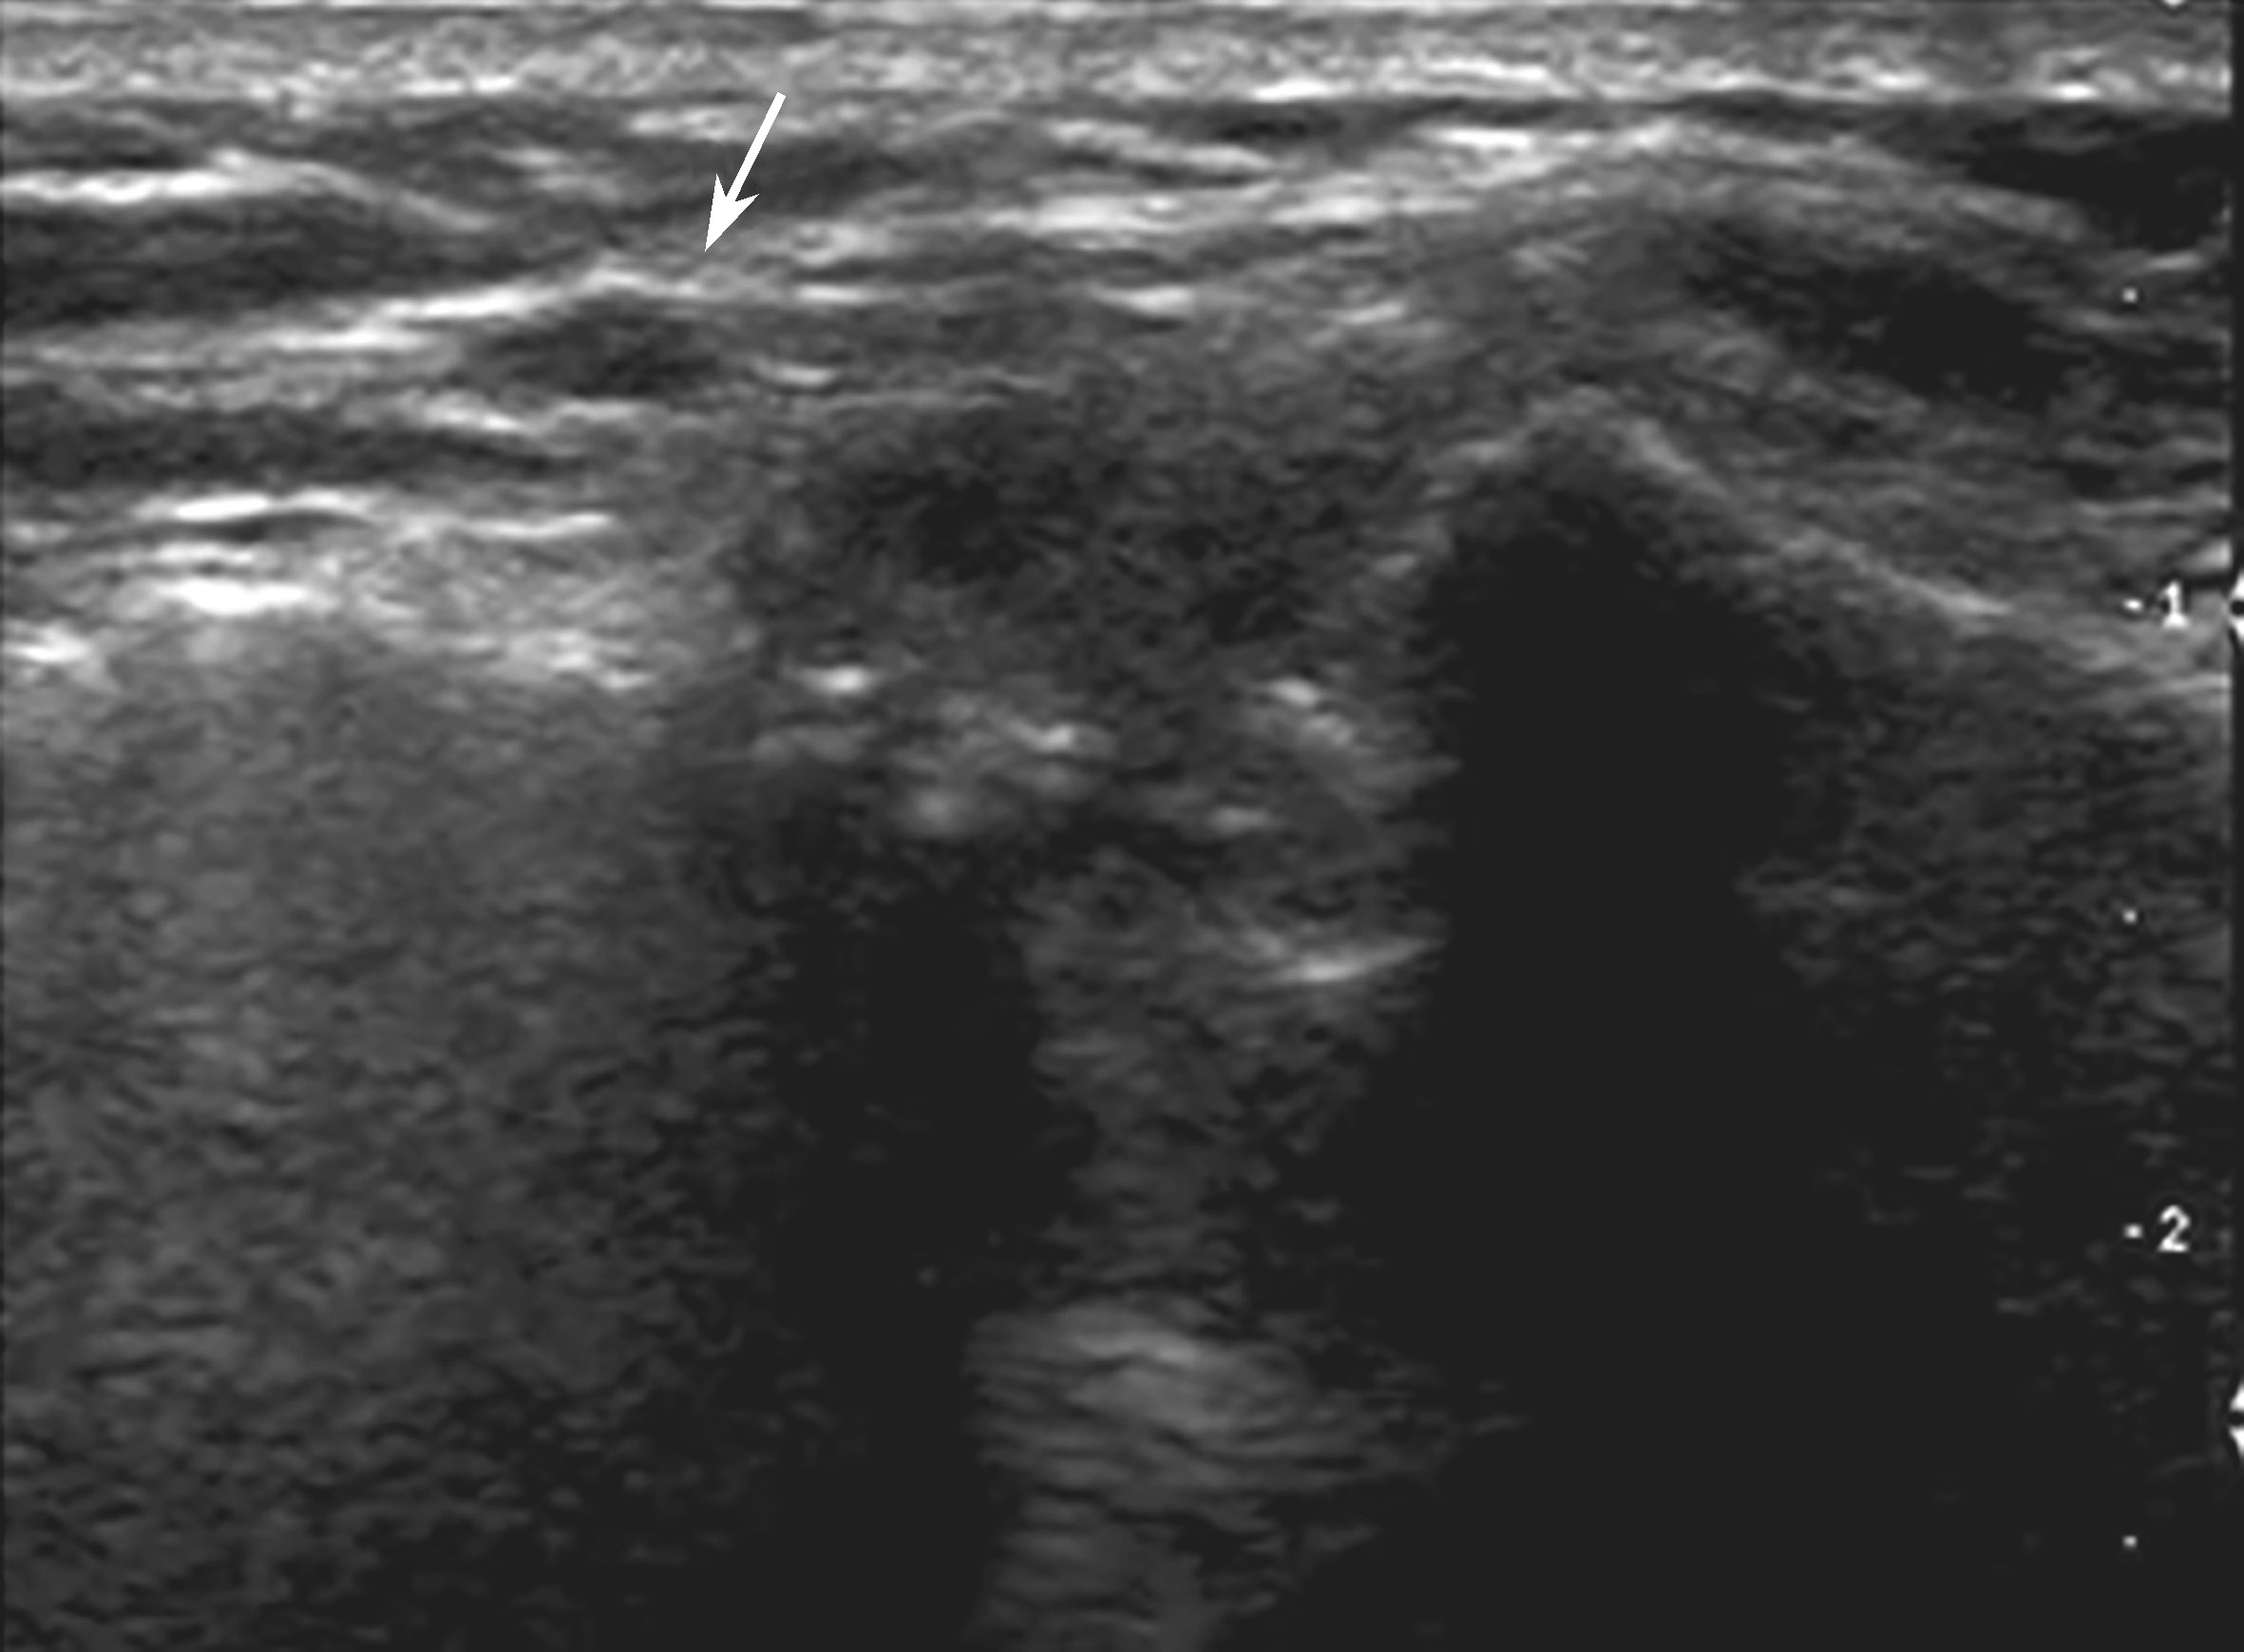

▲ 图2-4-2 超声引导下肩锁关节腔介入治疗超声图(一)

平面内进针法,箭头:穿刺针